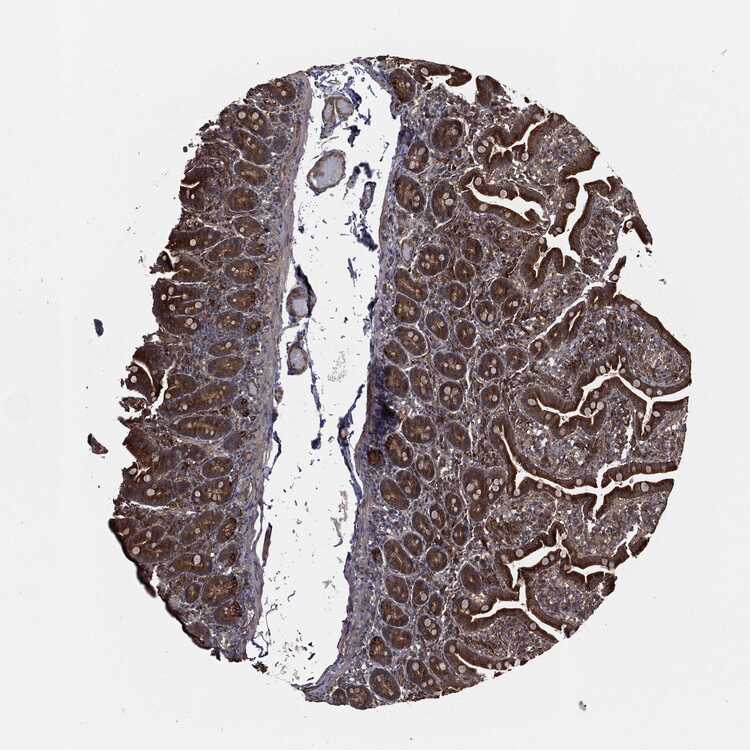

SMALL INTESTINE - Antibody stainingi

Antibody staining in the annotated cell types in the current human tissue is reported as not detected, low, medium, or high, based on conventional immunohistochemistry profiling in selected tissues. This score is based on the combination of the staining intensity and fraction of stained cells.

Each image is clickable and will lead to virtual microscopy that enables deeper exploration of all samples and also displays staining intensity scores, fraction scores and subcellular localization as well as patient and tissue information for each sample.

Antibody HPA041439Antibody HPA066153

Glandular cells MediumHigh